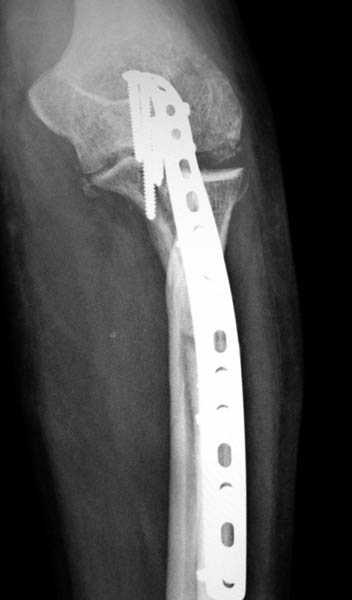

3 вариант

перелом с capitellum humerus и проксимальной трети улна